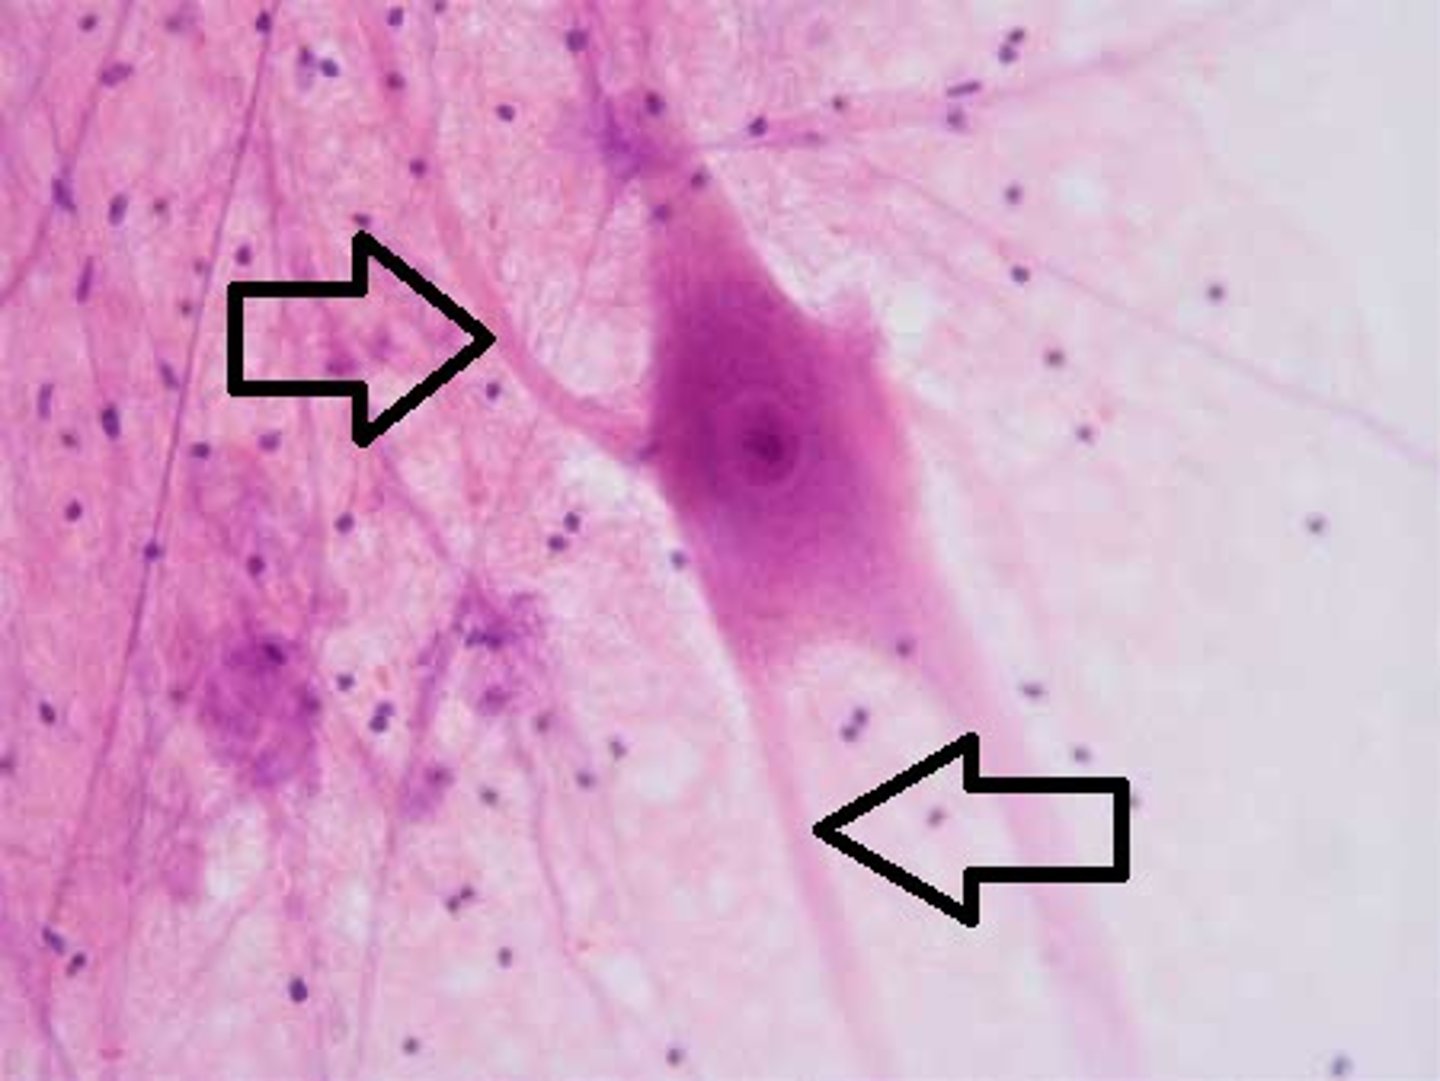

dendrites

receive messages from other cells

cell body

the cell's life support center

axon

A threadlike extension of a neuron that carries nerve impulses away from the cell body.

nervous tissue

neurons and neuroglia